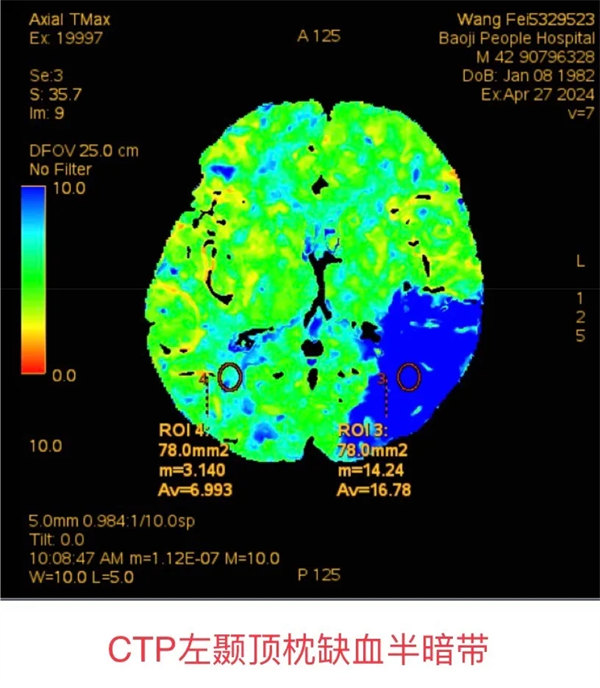

轉(zhuǎn)科第二天,王先生突然出現(xiàn)不能理解家人講話,答非所問,“上一秒還好好地和我交流,怎么突然就不行了”王先生的妻子焦急地說。侯卓醫(yī)生評(píng)估了病情后考慮新發(fā)腦梗死,NIHSS評(píng)分7分,并將病情立即上報(bào)科主任席聰。考慮到患者有上消化道出血病史,無法再次溶栓,侯卓醫(yī)師便安排王先生急診行顱腦CTA及灌注成像,同時(shí)請(qǐng)席聰評(píng)估介入取栓可能性,經(jīng)檢查,王先生左側(cè)大腦中動(dòng)脈M2段閉塞,有大范圍缺血灶,未見明顯梗死。